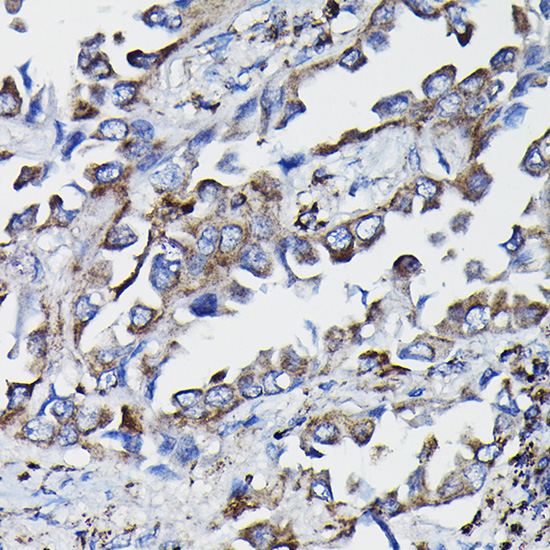

Immunohistochemistry of paraffin-embedded Human lung cancer with GSTK1 antibody diluted at 1:100